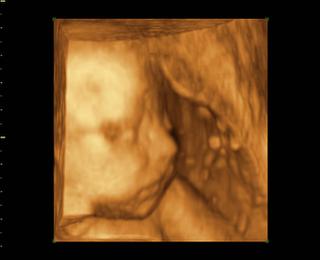

@14petulka88 Ja som pri prvom za fotky neplatila lebo som platila 1500 Sk za DVDčko, mám dve DVDčka jedno z 34 týždňa a jedno z 34t ýždňa. Tu len tak na ukážku dve fotky môjho Danielka z 3Dčka.